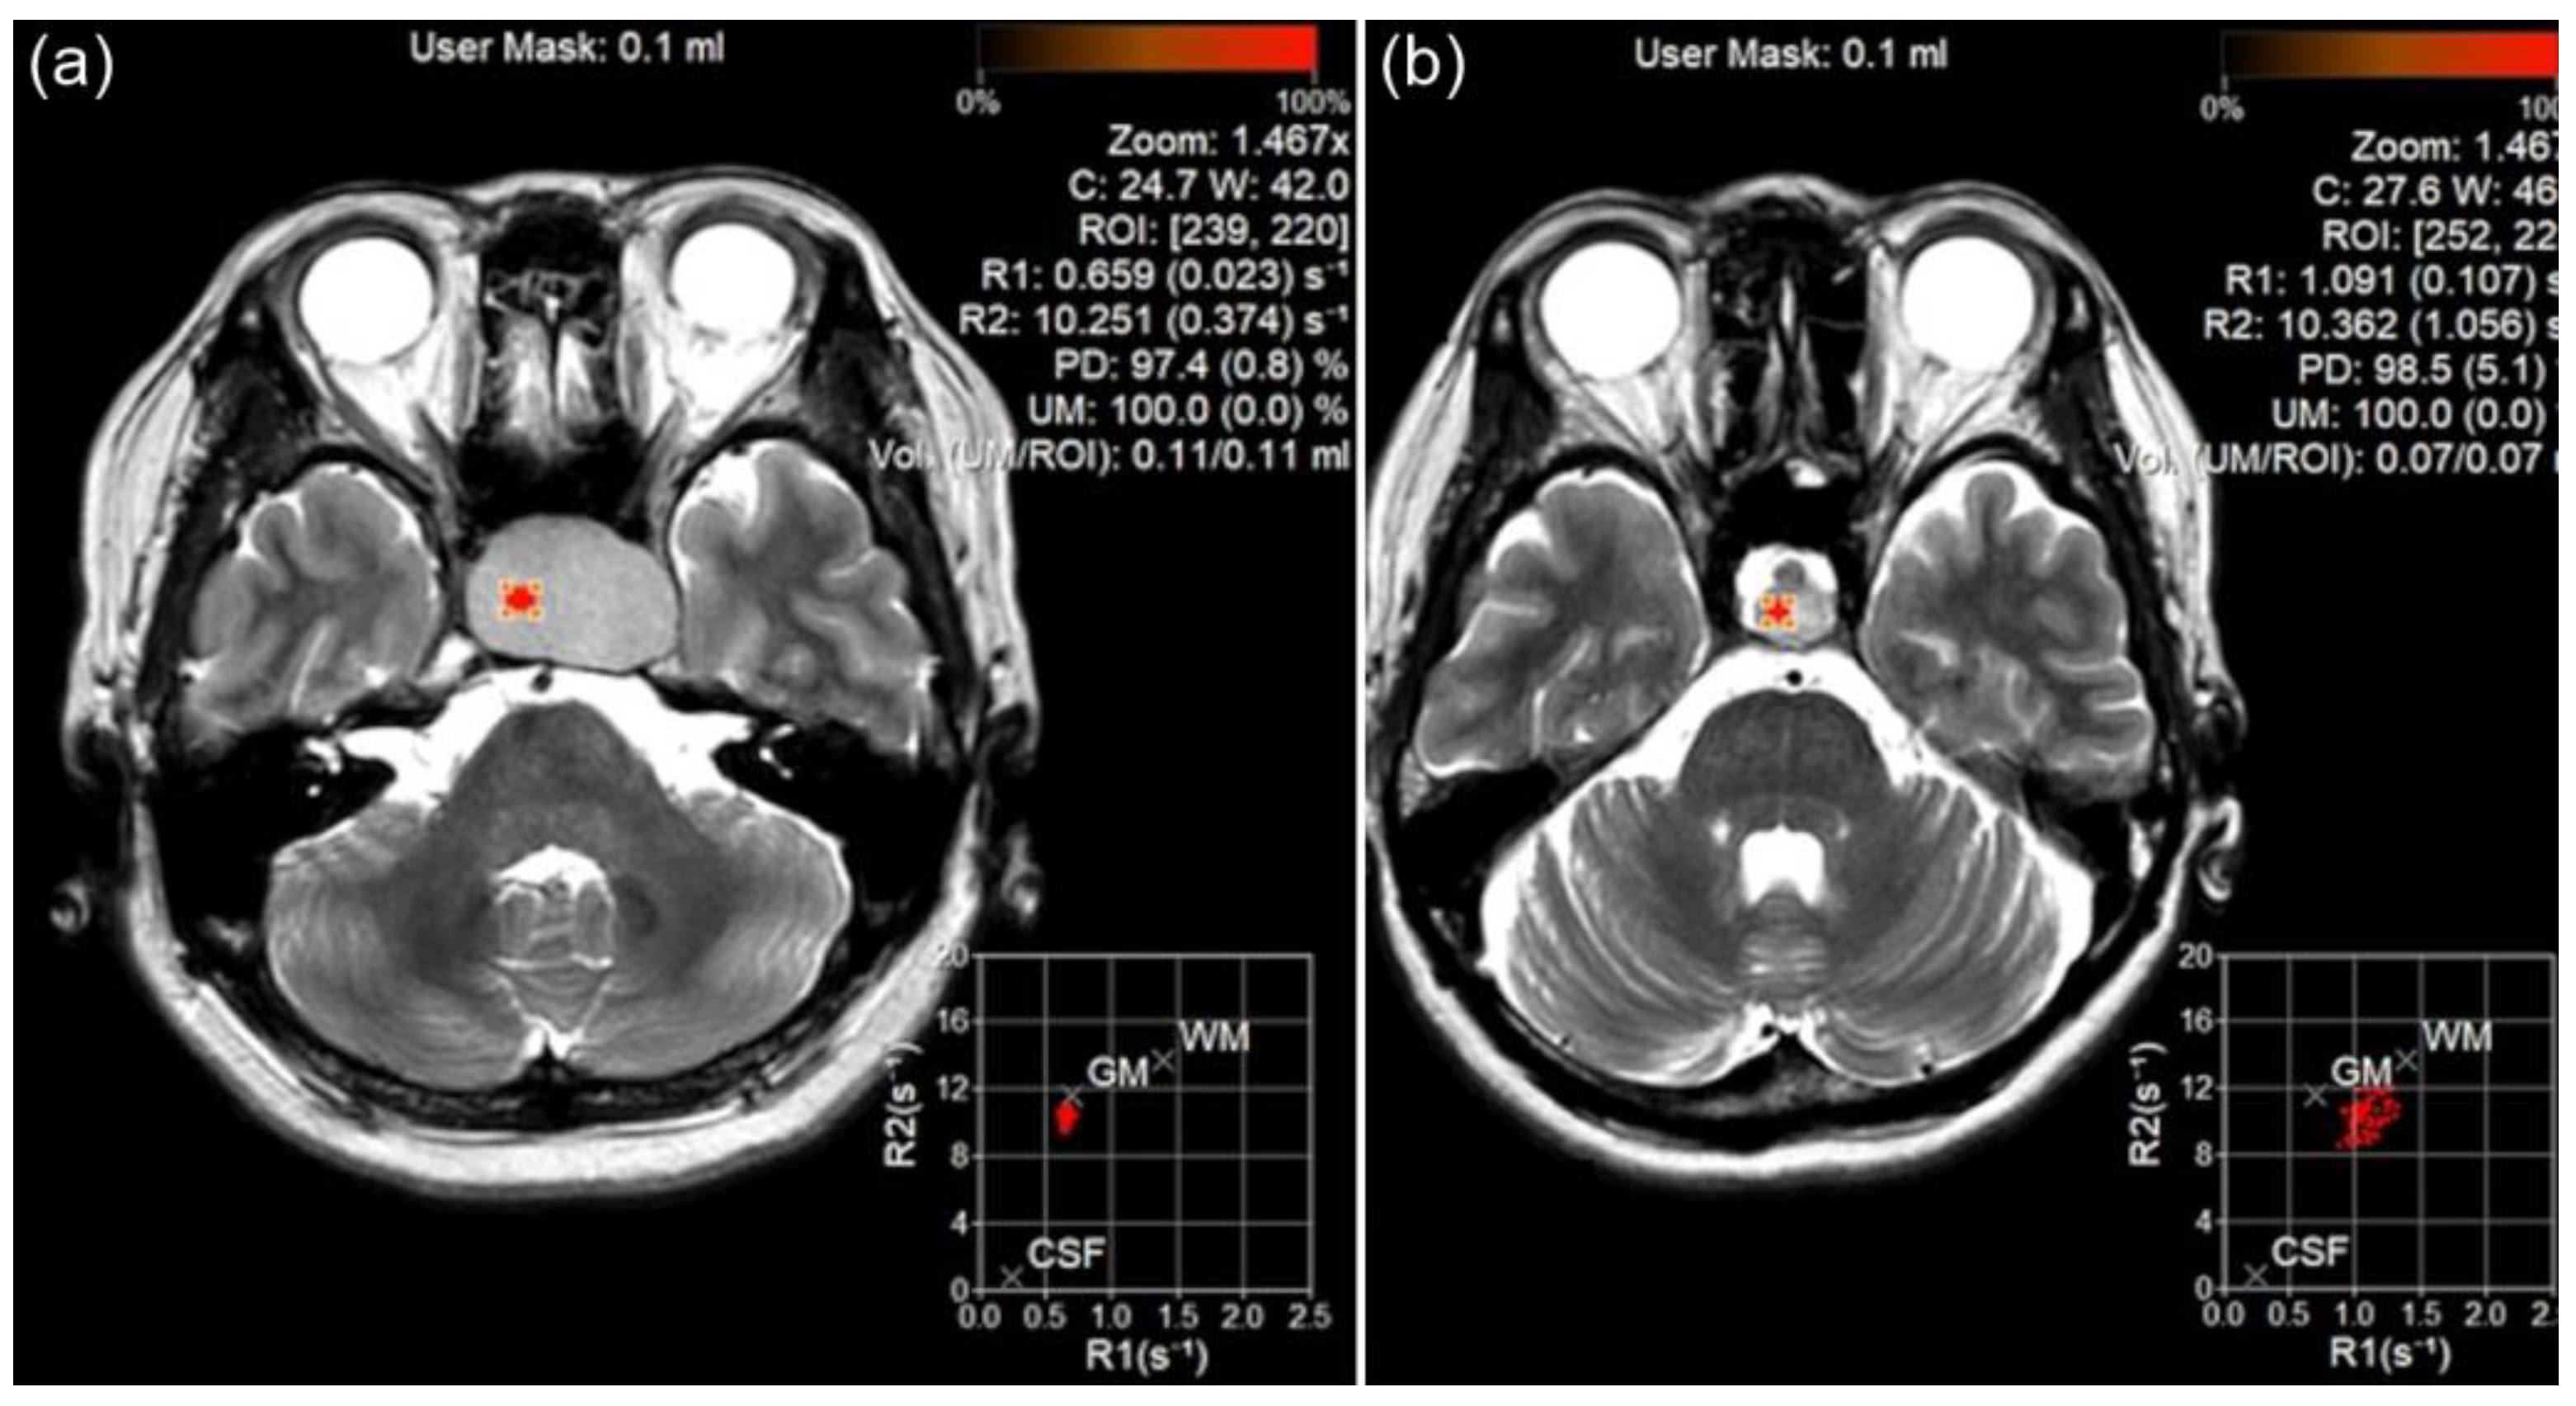

Quantitative analyses (measurements of R1 and R2 relaxation rates) were conducted by a neuroradiologist (B.L.) using circular region-of-interest (ROI) measurements of MAGiC images. The neuroradiologist manually placed multiple round or oval ROIs in the lesions and the median value of the multiple ROIs was used (Figure 1). The radiologist placed a large ROI covering the entire lesion and designated multiple smaller ROIs for each individual component of heterogeneous lesions. This approach was adopted to enhance the representation of the overall quantitative values of the lesions.

Figure 1.

Region of interest (ROI) measurement for pituitary adenoma (PA) and Rathke’s cleft cyst (RCC) using magnetic resonance imaging compilation (MAGiC) image. The ROI was placed on PA (a) and RCC (b), and T1 and T2 relaxation rates were calculated.